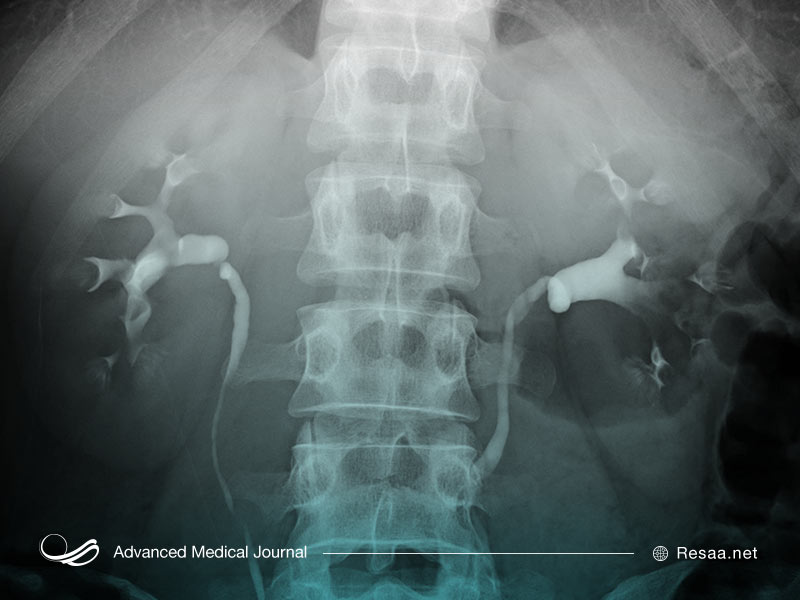

Pyelogram داخل وریدی

در پیلوگرام وریدی که اوروگرام داخل وریدی نیز نامیده میشود، یک ارائه دهنده خدمات بهداشتی رنگ خاصی را به نام ماده حاجب به داخل ورید بازوی بیمار تزریق میکند. ماده حاجب از طریق بدن به کلیهها منتقل میشود. کلیهها ماده حاجب را از طریق ادرار دفع میکنند که این موضوع باعث میشود ادرار از طریق اشعه ایکس قابل مشاهده باشد. یک pyelogram داخل وریدی میتواند هرگونه انسداد در دستگاه ادراری را نشان دهد و کیستها به صورت خوشههای نور ظاهر میشوند.